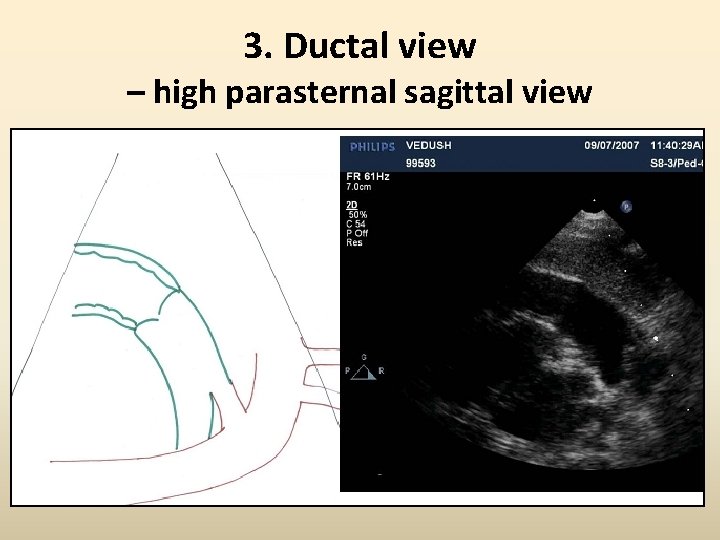

3. Ductal view – high parasternal sagittal view